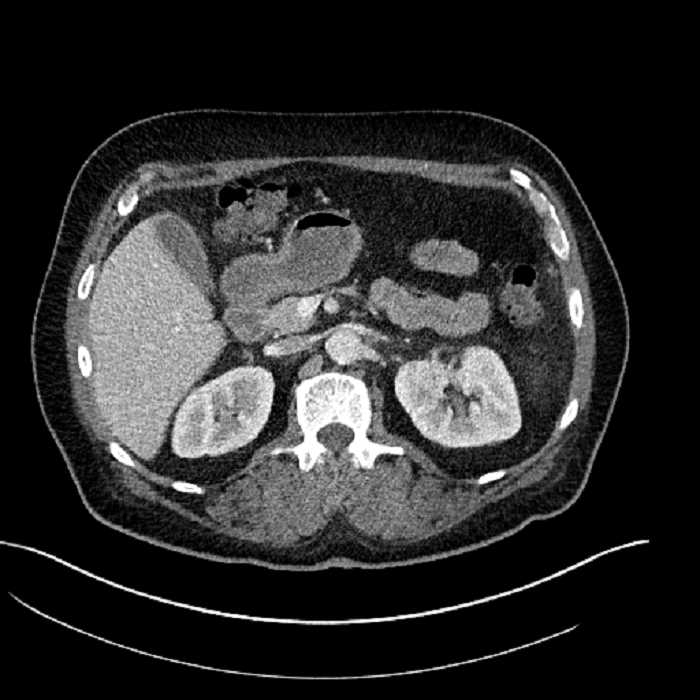

• Large fluid density structure in hepatic segments 7 and 8 measuring 10 x 7 x 7 cm with internal septation and circumferential ill-defined low density compatible with edema

• Peripherally enhancing subcapsular collections along the anterior margin of the left hepatic lobe measuring 3 x 1 cm and 2 x 1 cm

• Clearly marginated fluid density structure in segment 7 and several other scattered tiny hypodensities, which likely represent cysts

Acute sigmoid diverticulitis complicated by a small contained perforation and a large abscess in the right hepatic lobe. Additional small subcapsular abscesses along the anterior margin of the left hepatic lobe.

• The classic CT imaging appearance is a double target sign with internal low density surrounded by an internal enhancing rim (capsule) and a low density external rim (edema)

Hepatic abscess showing the double target sign with low density internally surrounded by a thin inner enhancing rim (red arrow) and ill-defined outer low density rim (yellow arrow). Blue arrow indicates an internal septation. Red arrows: additional smaller subcapsular abscesses. Red arrow: focal contained perforation associated with diverticulitis.